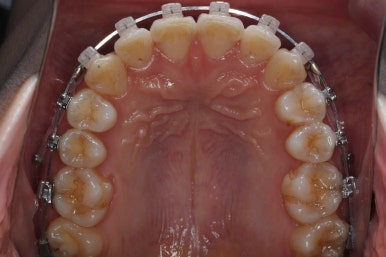

몇 달간의 마무리과정을 거치고 드디어 장치를 제거하였습니다.

위아래 앞니는 다시 틀어지지 말라고 유지철사를 붙였습니다.

위에는 탈착이 가능한 유지장치도 사용합니다. 2중으로 안전장치를 하는 것이죠.

치아는 매우 가지런해졌고, 과개교합도 개선이 되었으며 뻐드러진 앞니 각도도 정상적으로 회복이 되었습니다.